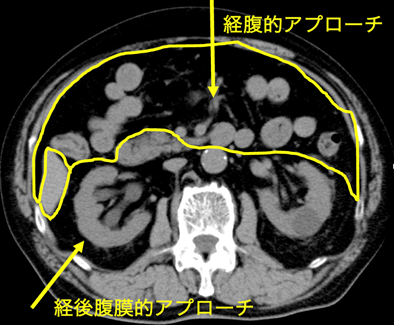

泌尿器科で扱う臓器は副腎、腎、尿管、膀胱、前立腺、尿道、精巣(睾丸)などです。これらの臓器のある場所は「腹膜」という膜構造で仕切られ、胃腸や肝臓などの消化器臓器の背中側「後腹膜腔」に位置します。

副腎や腎に対する手術は、直接背中側から目的の臓器に到達する方法(経後腹膜到達法)、「腹腔」と呼ばれる消化器臓器のある場所を経てそれらを除けながら後ろにある臓器に到達する方法があります(経腹到達法)。

腹部に3-4箇所小さな孔をあけ筒を挿入します。これをポートとよびます。経後腹膜到達法の場合、後腹膜腔を風船でふくらませ空間を作成した後、後腹膜腔を炭酸ガスでふくらませ内部がよく観察できるようにします。